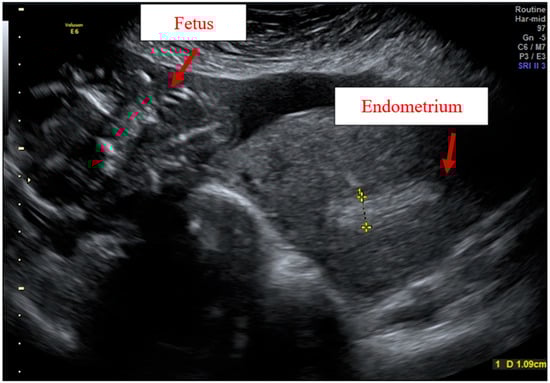

Case Report

Adenomyosis Ultrasound Diagnosis and Classification